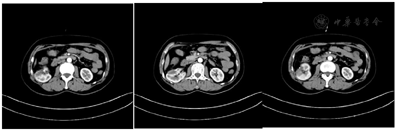

病例1专科检查:双肾区无隆起,双肾及输尿管移行区无叩压痛,膀胱区不充盈、无压痛,外生殖器无异常,尿道外口无脓性分泌物。2020年6月23日超声检查,超声所见:双侧肾上腺部位多断面超声扫查,未见明显异常回声。肾脏:右肾长108 mm;左肾长108 mm。双肾形态正常,肾实质与肾窦比例正常,肾盂、肾盏未见明显扩张。右肾下极皮质见一囊实混合性回声,大小约34 mm×31 mm×30 mm。形态规则,边界清晰,内见多发点状强回声,内未见明显血流。输尿管:双侧输尿管不扩张。超声提示:右肾囊实混合性回声,复杂囊肿?2020年6月26日,多排CT腹部平扫(中,下腹)组合,CT所见:右肾下段腹侧见结节状稍低密度影,直径约2.5 cm,其内见斑点状钙化灶。左肾大小、形态正常,两肾实质内未见异常密度灶,双侧肾盂、肾盏及输尿管无明显扩张积水征象,内无异常密度影。肾周脂肪间隙清晰。双侧肾上腺形态、大小未见明显异常(图1)。

2020年6月29日多排CT肾肿瘤CTA(优维显)。CT所见:右肾中下极前部可见一约2.8 cm×2.1 cm×2.7 cm大小的低密度灶(T),内见少许分隔,病灶边界尚清,局部膨出于肾脏表面。右肾动脉提前发出一支分支至右肾上极;远端发出上、下两分支:上支继而发出前、后两支"上-前支远段至右肾中上极前部;上-后支远段至右肾中上极后部"。下支在肾门处发出前上、后下两分支:下-前支(A)先发出一小分支进入病灶(T),继而发出前、后两支:下-前上-前支远段进入病灶(T);下-前上-后支远段至右肾下极前部。下-后下支远段至右肾下极。考虑:右肾中下极占位,肾癌可能(图2)。